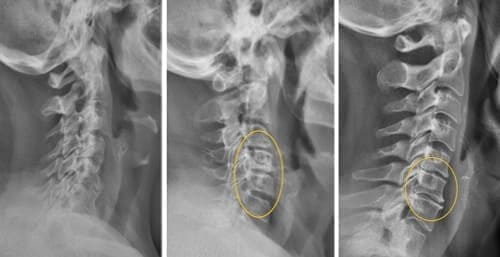

Mire esta radiografía. Es la columna de una persona de 44 años, pero parece la de un anciano. Antes, este tipo de daño aparecía después de los 60 años y, hoy, es muy común en personas de poco más de 40. Estos cambios progresan con la edad, y ignorarlos amenaza con una pérdida completa de movilidad.

Columna de un paciente de 44 años: todo comenzó con un dolor simple, pero en una semana apareció la hernia, y en dos semanas — desplazamiento de las vértebras, compresión de nervios y silla de ruedas.